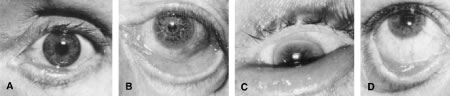

| Ectropion is an eversion of the eyelid away from the globe. It is classified

according to its anatomic features as involutional, cicatricial, tarsal, congenital, or

paralytic (Fig. 2). Surgical approaches can be directed toward the underlying etiologic